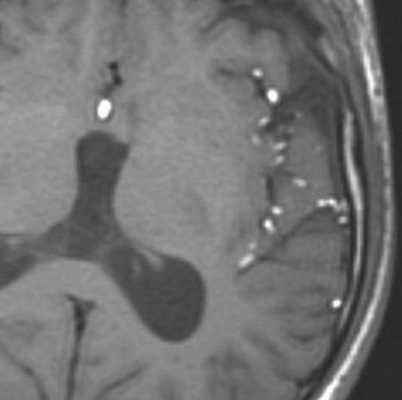

МРТ головного мозга. Т1-взвешенная аксиальная МРТ. Прорыв дермоидной кисты в субарахноидальное пространство.

Дермоидные кисты встречаются реже эпидермоидных, составляя около 0,3 % от внутричерепных образований. Обычно выявляются в возрасте между 10 и 20 годами. Морфологически от эпидермоидов их отличает наличие эктодермальных элементов - волосяных фолликулов, потовых желёз и т.д. Типично они расположены по средней линии (в отличие от эпидермоидов, которые чаще внеосевые): в супраселлярной цистерне, субфронтально, вокруг моста и, очень редко парапинеально, периорбитально, в IV желудочке, в области конского хвоста и интрадиплоидно. От эпидермоидных кист на МРТ головного мозга их отличает только выраженная неоднородность структуры, кроме того, они всегда яркие на Т1-зависимых МРТ головного мозга за счёт большого содержания липидов. При разрыве и прорыве в субарахноидальное пространство в нём появляется уровень, на Т1-зависимых МРТ головного мозга светлый жир плавает на ликворе.